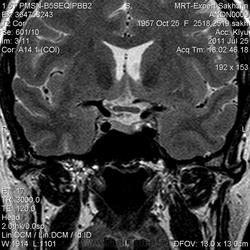

Как мы "динамичим"гипофиз

Женщина.6 лет назад выявлено образование левой доли нейрогипофиза.Пришла на контроль.

Постконтраст

Мне самой показался случай не совсем ясным, но динамик четко показывает участок с отставанием в контрастировании, воронка смещена вправо-о чем  думать бедному начинающему специалисту?